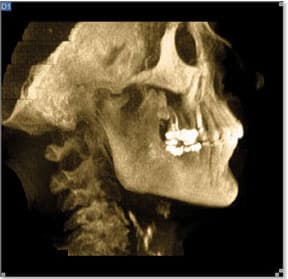

A Case Study of Acute Changes in Dental Occlusion: Digital CBCT Analysis

By DeWitt C. Wilkerson D.M.D. Fortunately, new advances in diagnostic imaging, such as Digital Cone Beam 3-D Technology, make it virtually impossible for pathology to escape diagnosis. To illustrate, let’s explore a challenging case to diagnose, beautifully exposed by digital CBCT technology. A 62-year-old Caucasian female presented with a chief complaint of progressive bite changes. Previously, all her teeth touched uniformly, but over the past 18 months this had gradually changed. The result was an open bite that extended from teeth #2–13, and a facial asymmetry with the mandibular plane of occlusion visibly canted significantly downward on the right side. She reported no pain; the left TM Joint felt normal